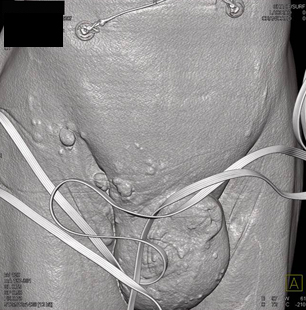

In this patient with known colon cancer the soft tissue masses are most likely

metastatic colon cancer to the subcutaneous tissue